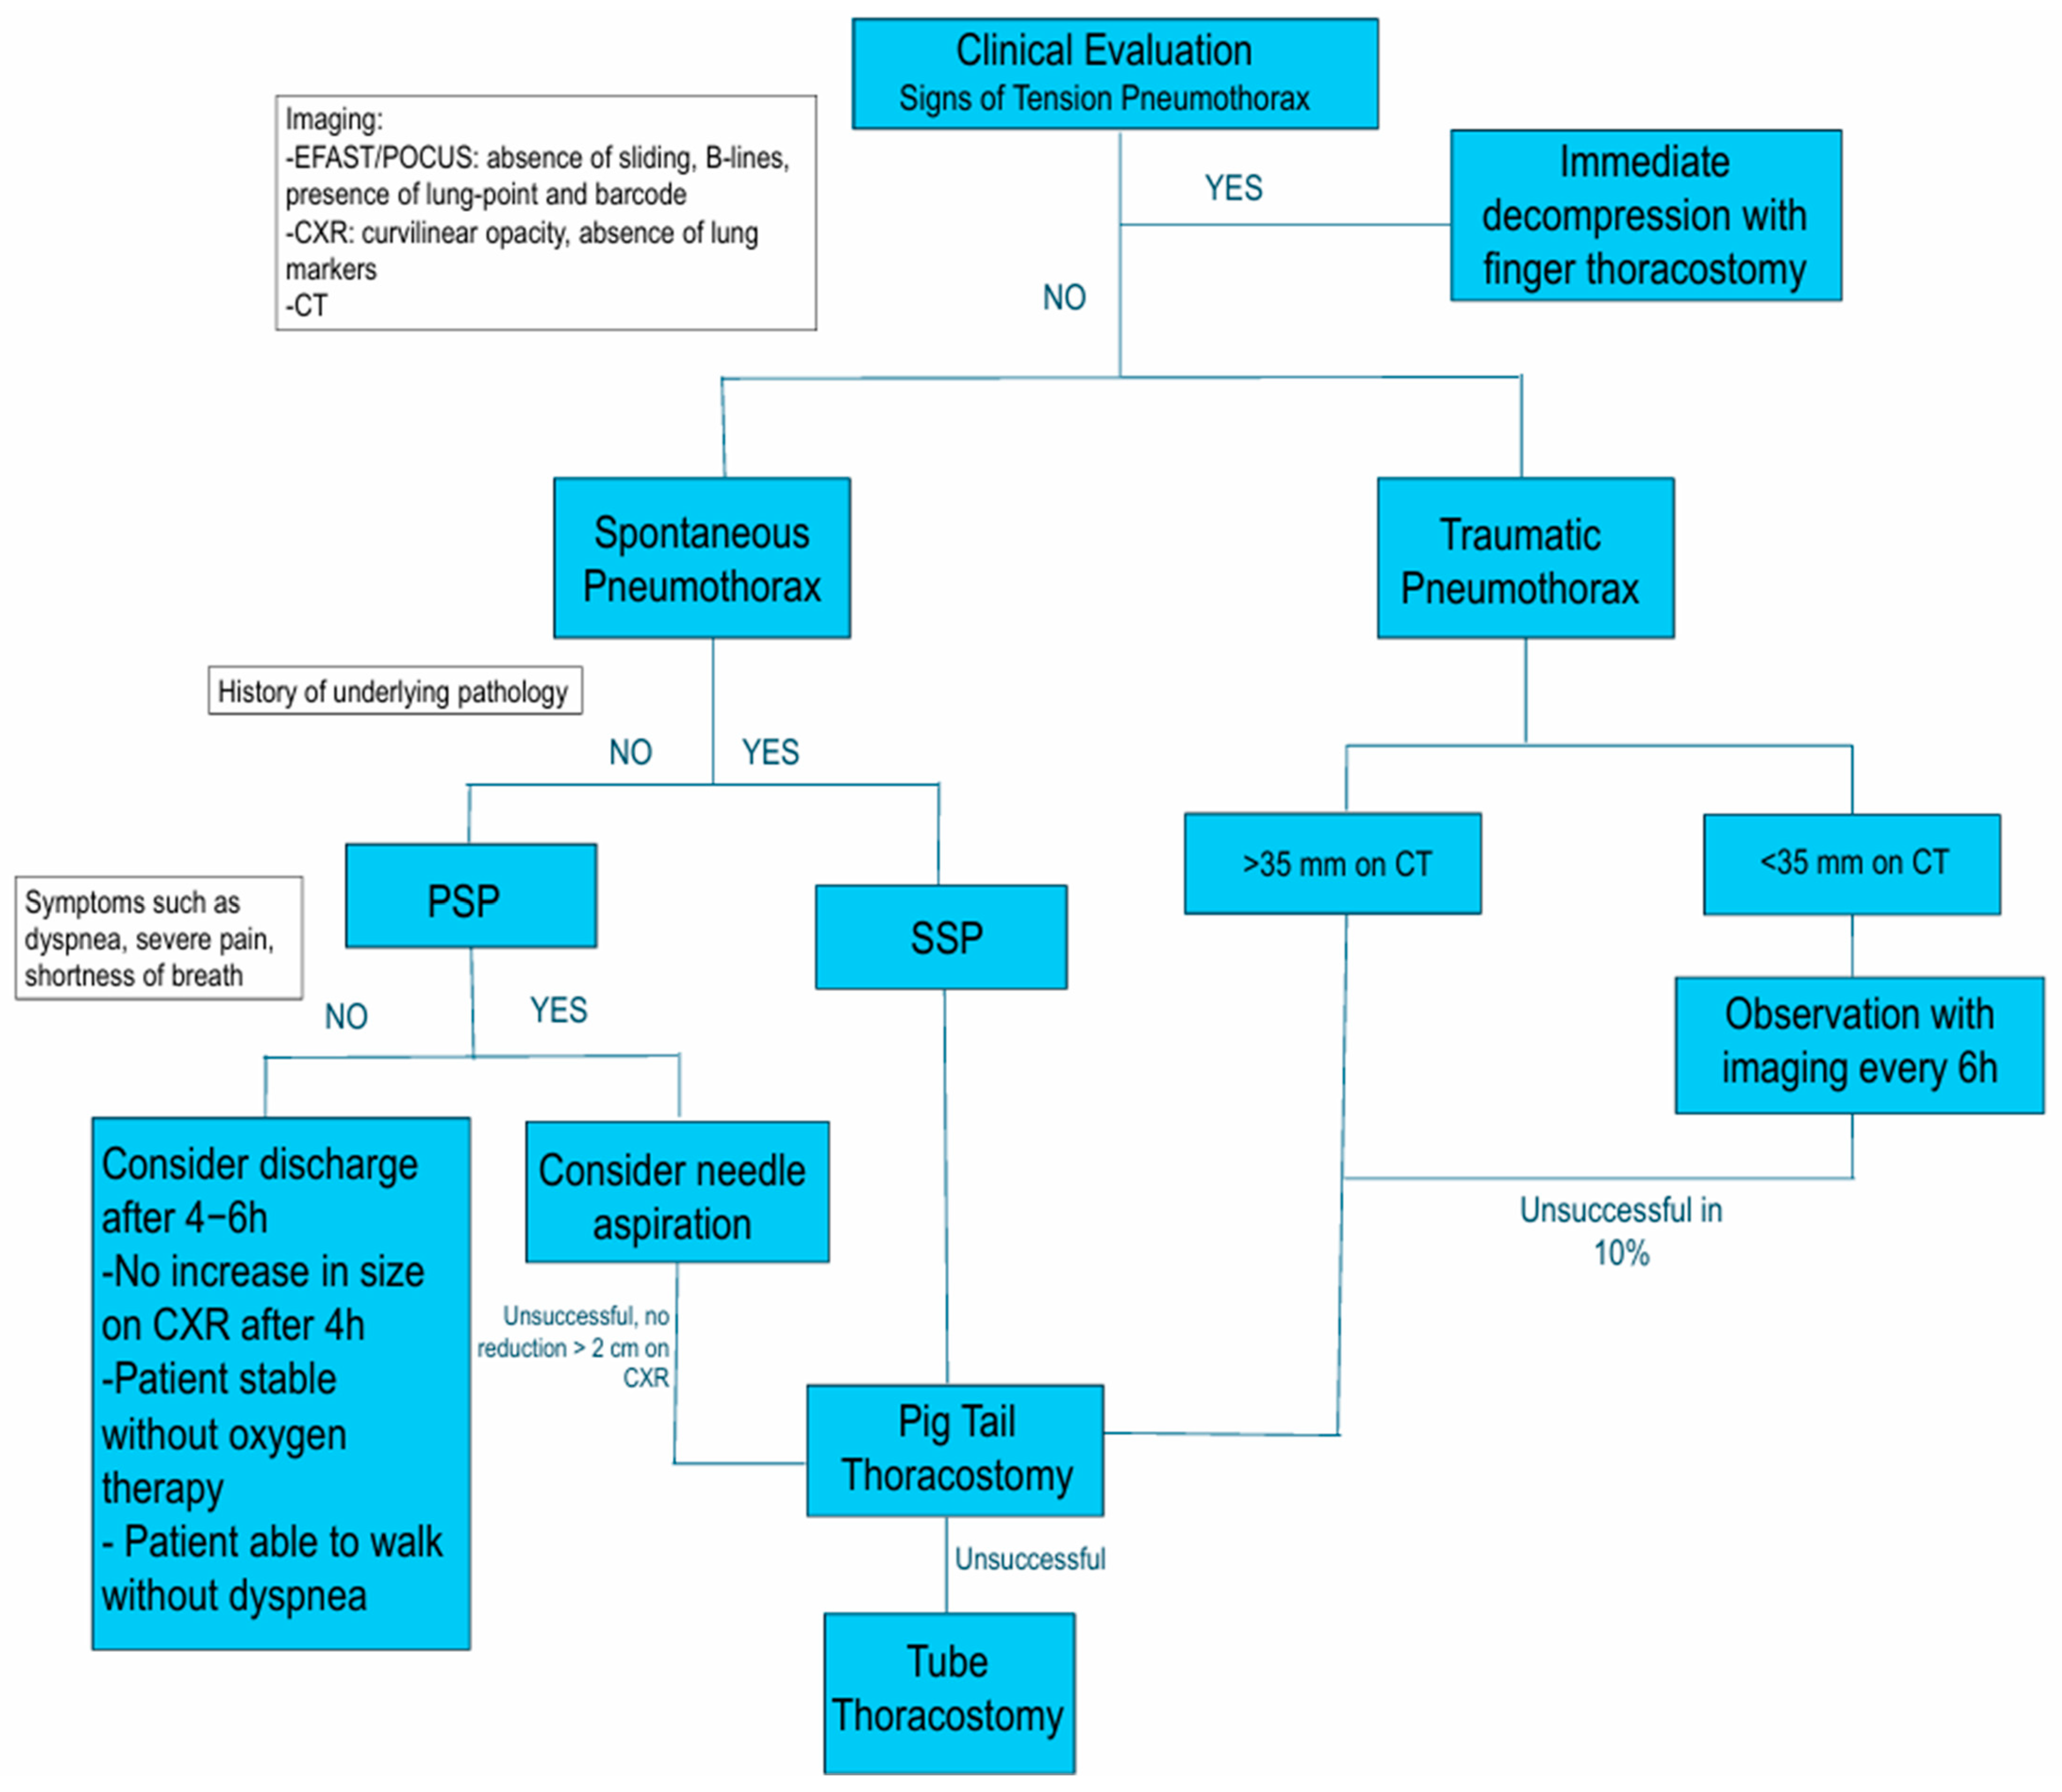

4. Treatment

4.1. Needle Decompression and Aspiration

4.2. Chest Drainage

4.4. Conservative Management

5. Conclusions